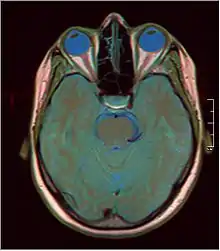

De nombreuses structures cérébrales et processus physiologiques sont impliqués dans la souffrance. Diverses hypothèses tentent de rendre compte de l'expérience de la souffrance. L'une d’elles, la théorie du chevauchement de la douleur suggère que la douleur physique et la douleur sociale, à savoir deux types radicalement différents de souffrances, partagent une base phénoménologique et neurologique commune. En effet, des observations en neuro-imagerie ont montré que le cortex cingulaire s’active quand l’individu souffre de détresse sociale ou de douleur physique[4].